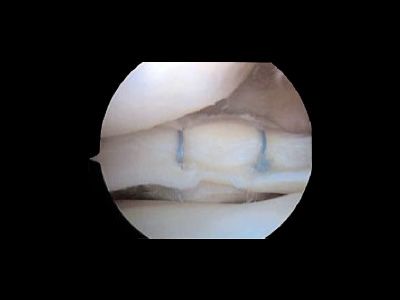

• Ma il vantaggio più importante è che viene asportata solo la parte lesionata del menisco, lasciando in sede la parte integra o dove possibile si esegue una riparazione (sutura meniscale)

La durata dell’intervento è di circa 15 - 20 min. durante i quali si procederà all’asportazione della parte di menisco lesionata o alla sutura ed all’esplorazione e palpazione delle restanti strutture articolari.